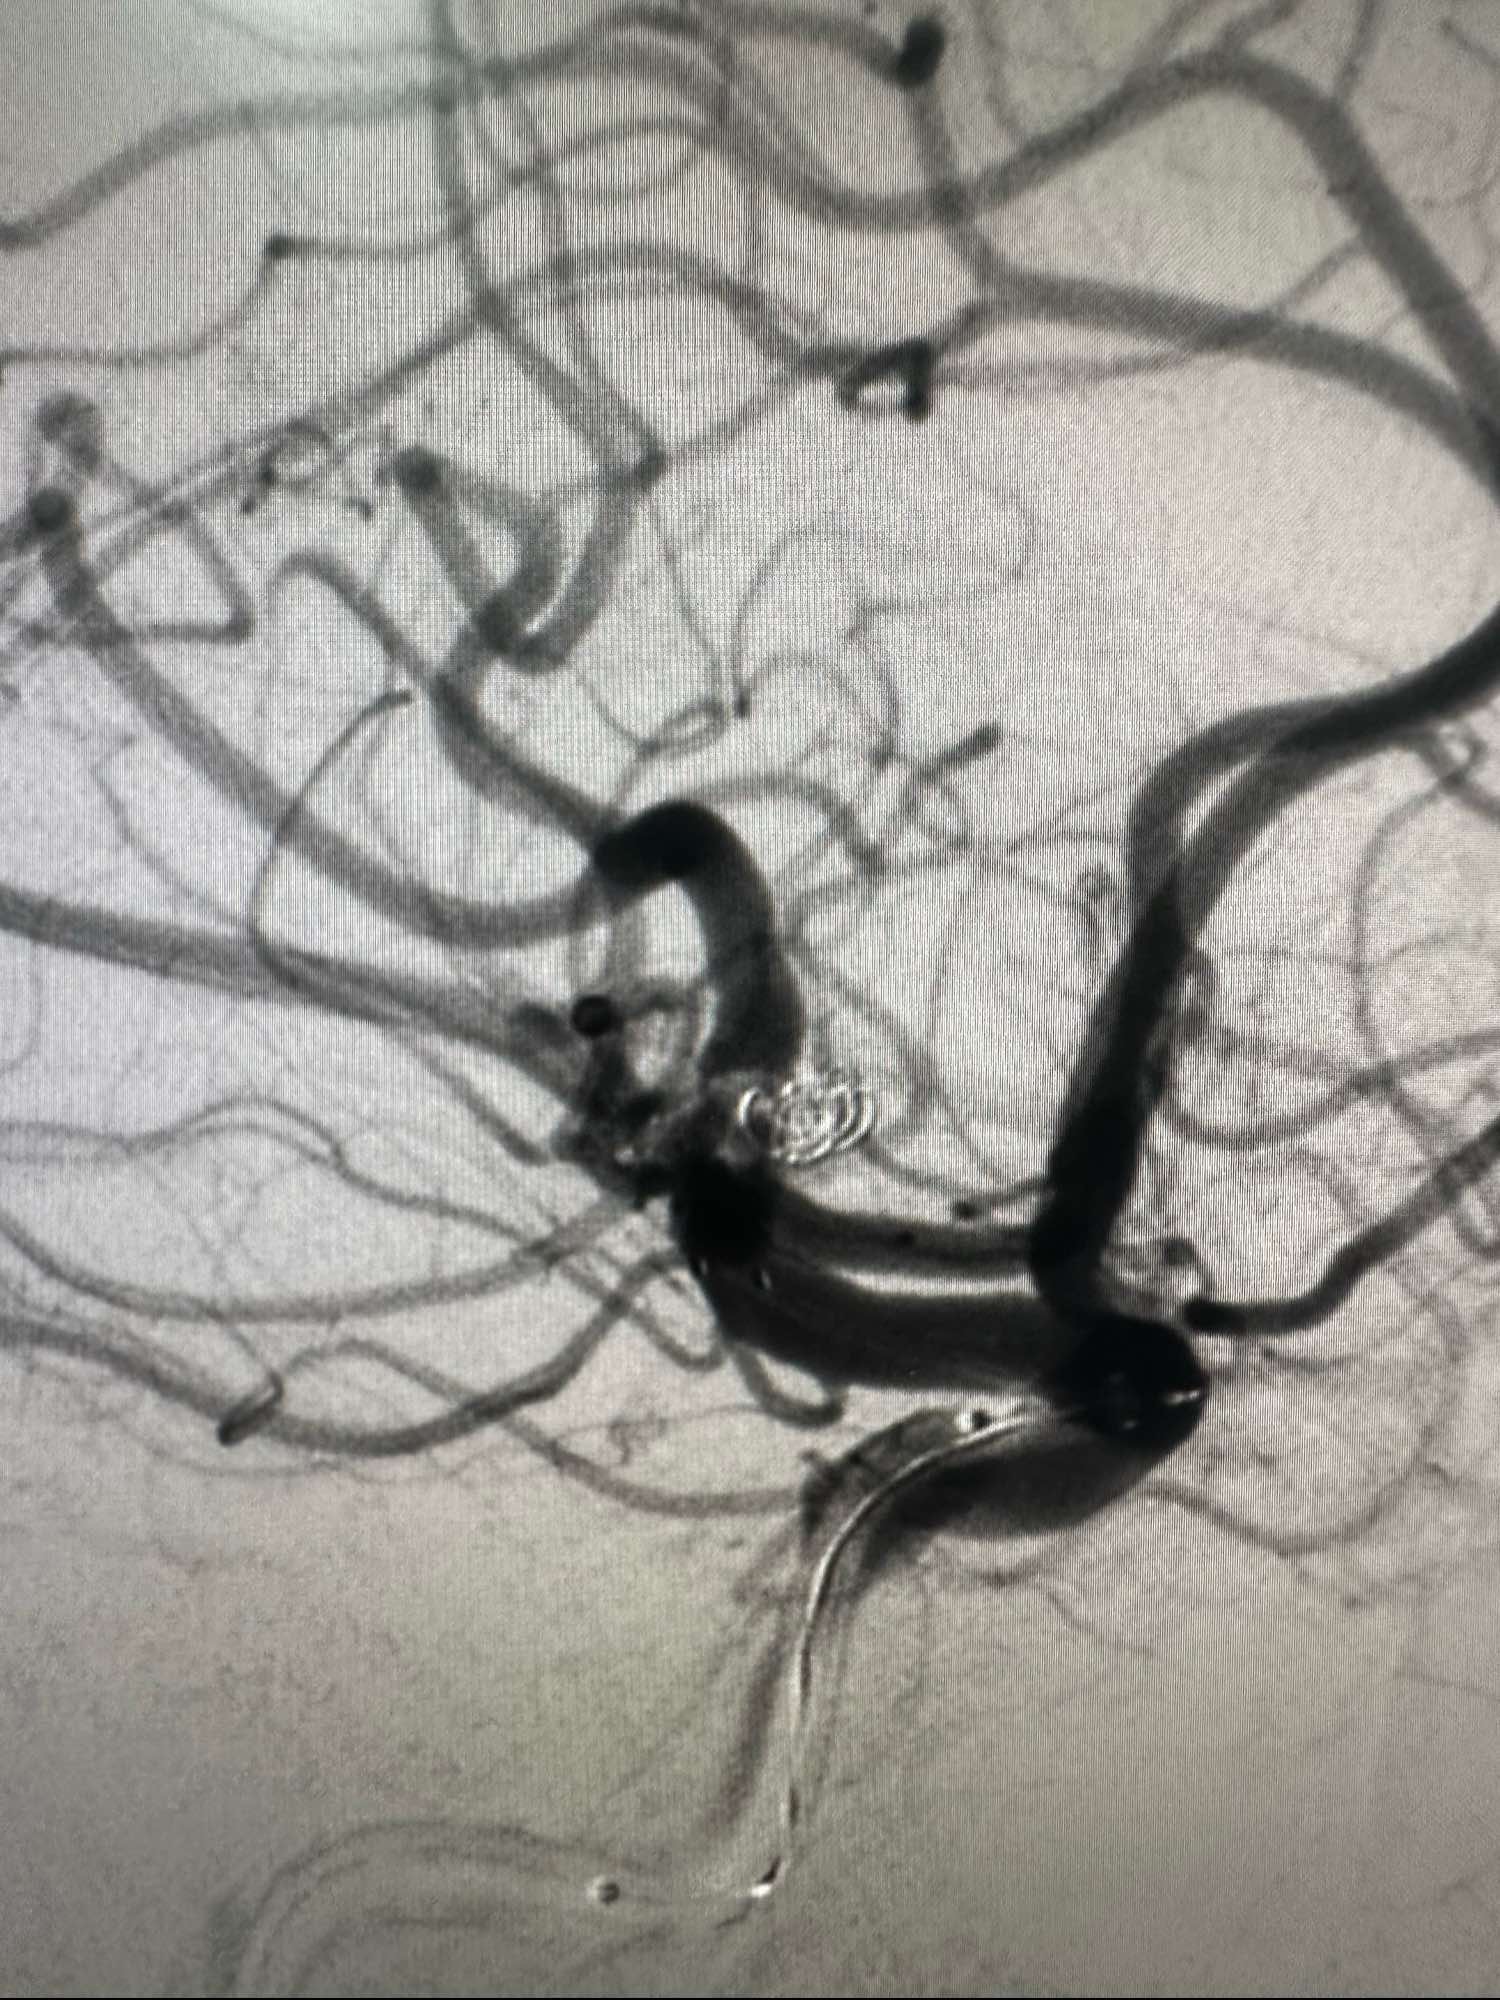

第一枚圈选择3*8的加奇的3D,出了几个襻后直接释放Atlas支架3*21

第一枚圈填塞后的形态,圈没有影响上干血流

第一枚圈的形态

后续再次填入2*4的加奇圈,另外一个角度造影见动脉瘤已经不显影

圈的形态

术中发现有血栓,动脉内直接给予新维林8ML,并静脉内持续泵入4ML再次造影见血栓已经完全消失

侧位,术后患者完全清醒,未见特殊异常